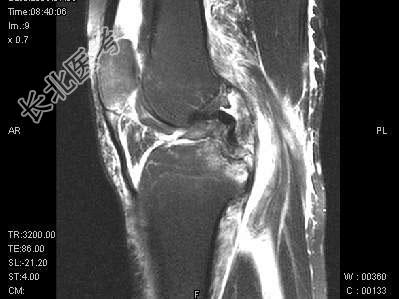

- 单项选择题女,17岁, 右膝关节有外伤史,现膝关节疼痛, 活动受限,结合图像, 最可能的诊断是 ( )

A、半月板撕裂

B、膝关节退变

C、未见异常

D、前交叉韧带断裂

E、后交叉韧带断裂